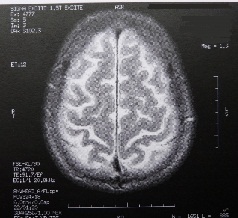

Sie sind hier: Startseite Nachrichten Gesundheit Studie: Falsche Schlafdauer lässt Gehirn bis zu sieben Jahre altern Bild: dido-ob / pixelio.de